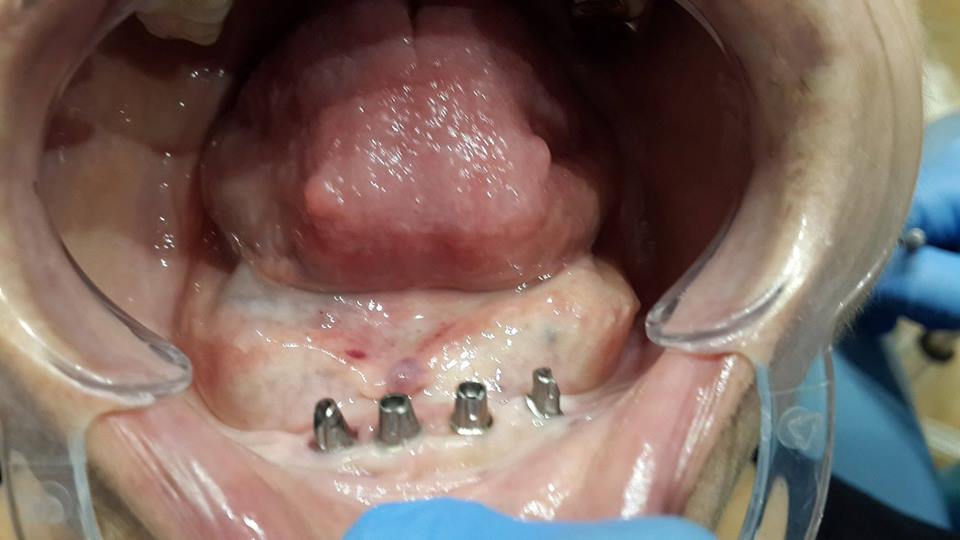

Prosthesis of the lower jaw on 4 implants

The patient was given a prosthetic lower jaw on 4 implants.

До имплантации